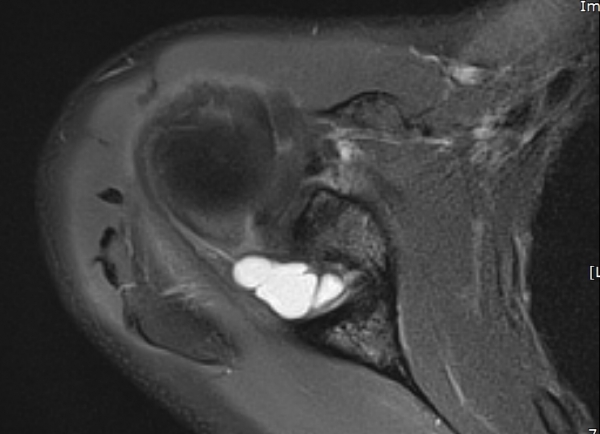

¾î±ú µÚÂÊ È¾´Ü¸é°Ë»ç¿¡¼­ °üÀý¿Í(glenoid) ³»Ãø¿¡¼­ ¸¹Àº ¾çÀÇ ¼ö¾×Àú·ù°¡ °üÂûµÈ´Ù(»çÁø 1, 2).

ÄÁº¤½ºÅ½ÃËÀÚ¸¦ ÀÌ¿ëÇÑ ¾î±ú µÚÂÊ È¾´Ü¸é°Ë»ç¿¡¼­ °üÀý¿Í ³»Ãø ¼ö¾× Àú·ù¿Í °üÀý¿Í¼ø ÆÄ¿­ÀÌ

°üÂûµÈ´Ù(»çÁø 3, 4, 5, 6).

ÀÚ±â°ø¸í°Ë»ç

large paralabral cyst